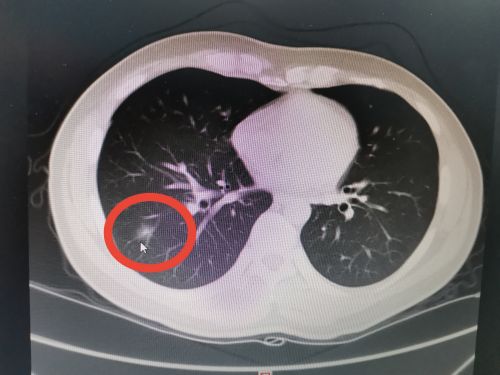

术前ct显示:右肺磨玻璃样结节。